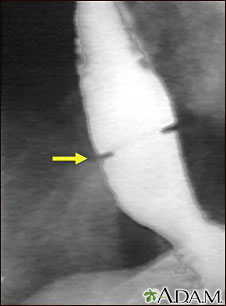

Radiografía del anillo de Schatzki

Se ha ingerido una solución con un medio de contraste (bario), el cual es visible en las radiografías que se han tomado del esófago (tránsito esofagogastroduodenal). Hay un estrechamiento cerca del estómago (señalada por la flecha). Este anillo de tejido no canceroso (anillo de Schatzki) puede causar problemas para deglutir (disfagia) y se puede tratar con la dilatación de dicho estrechamiento.